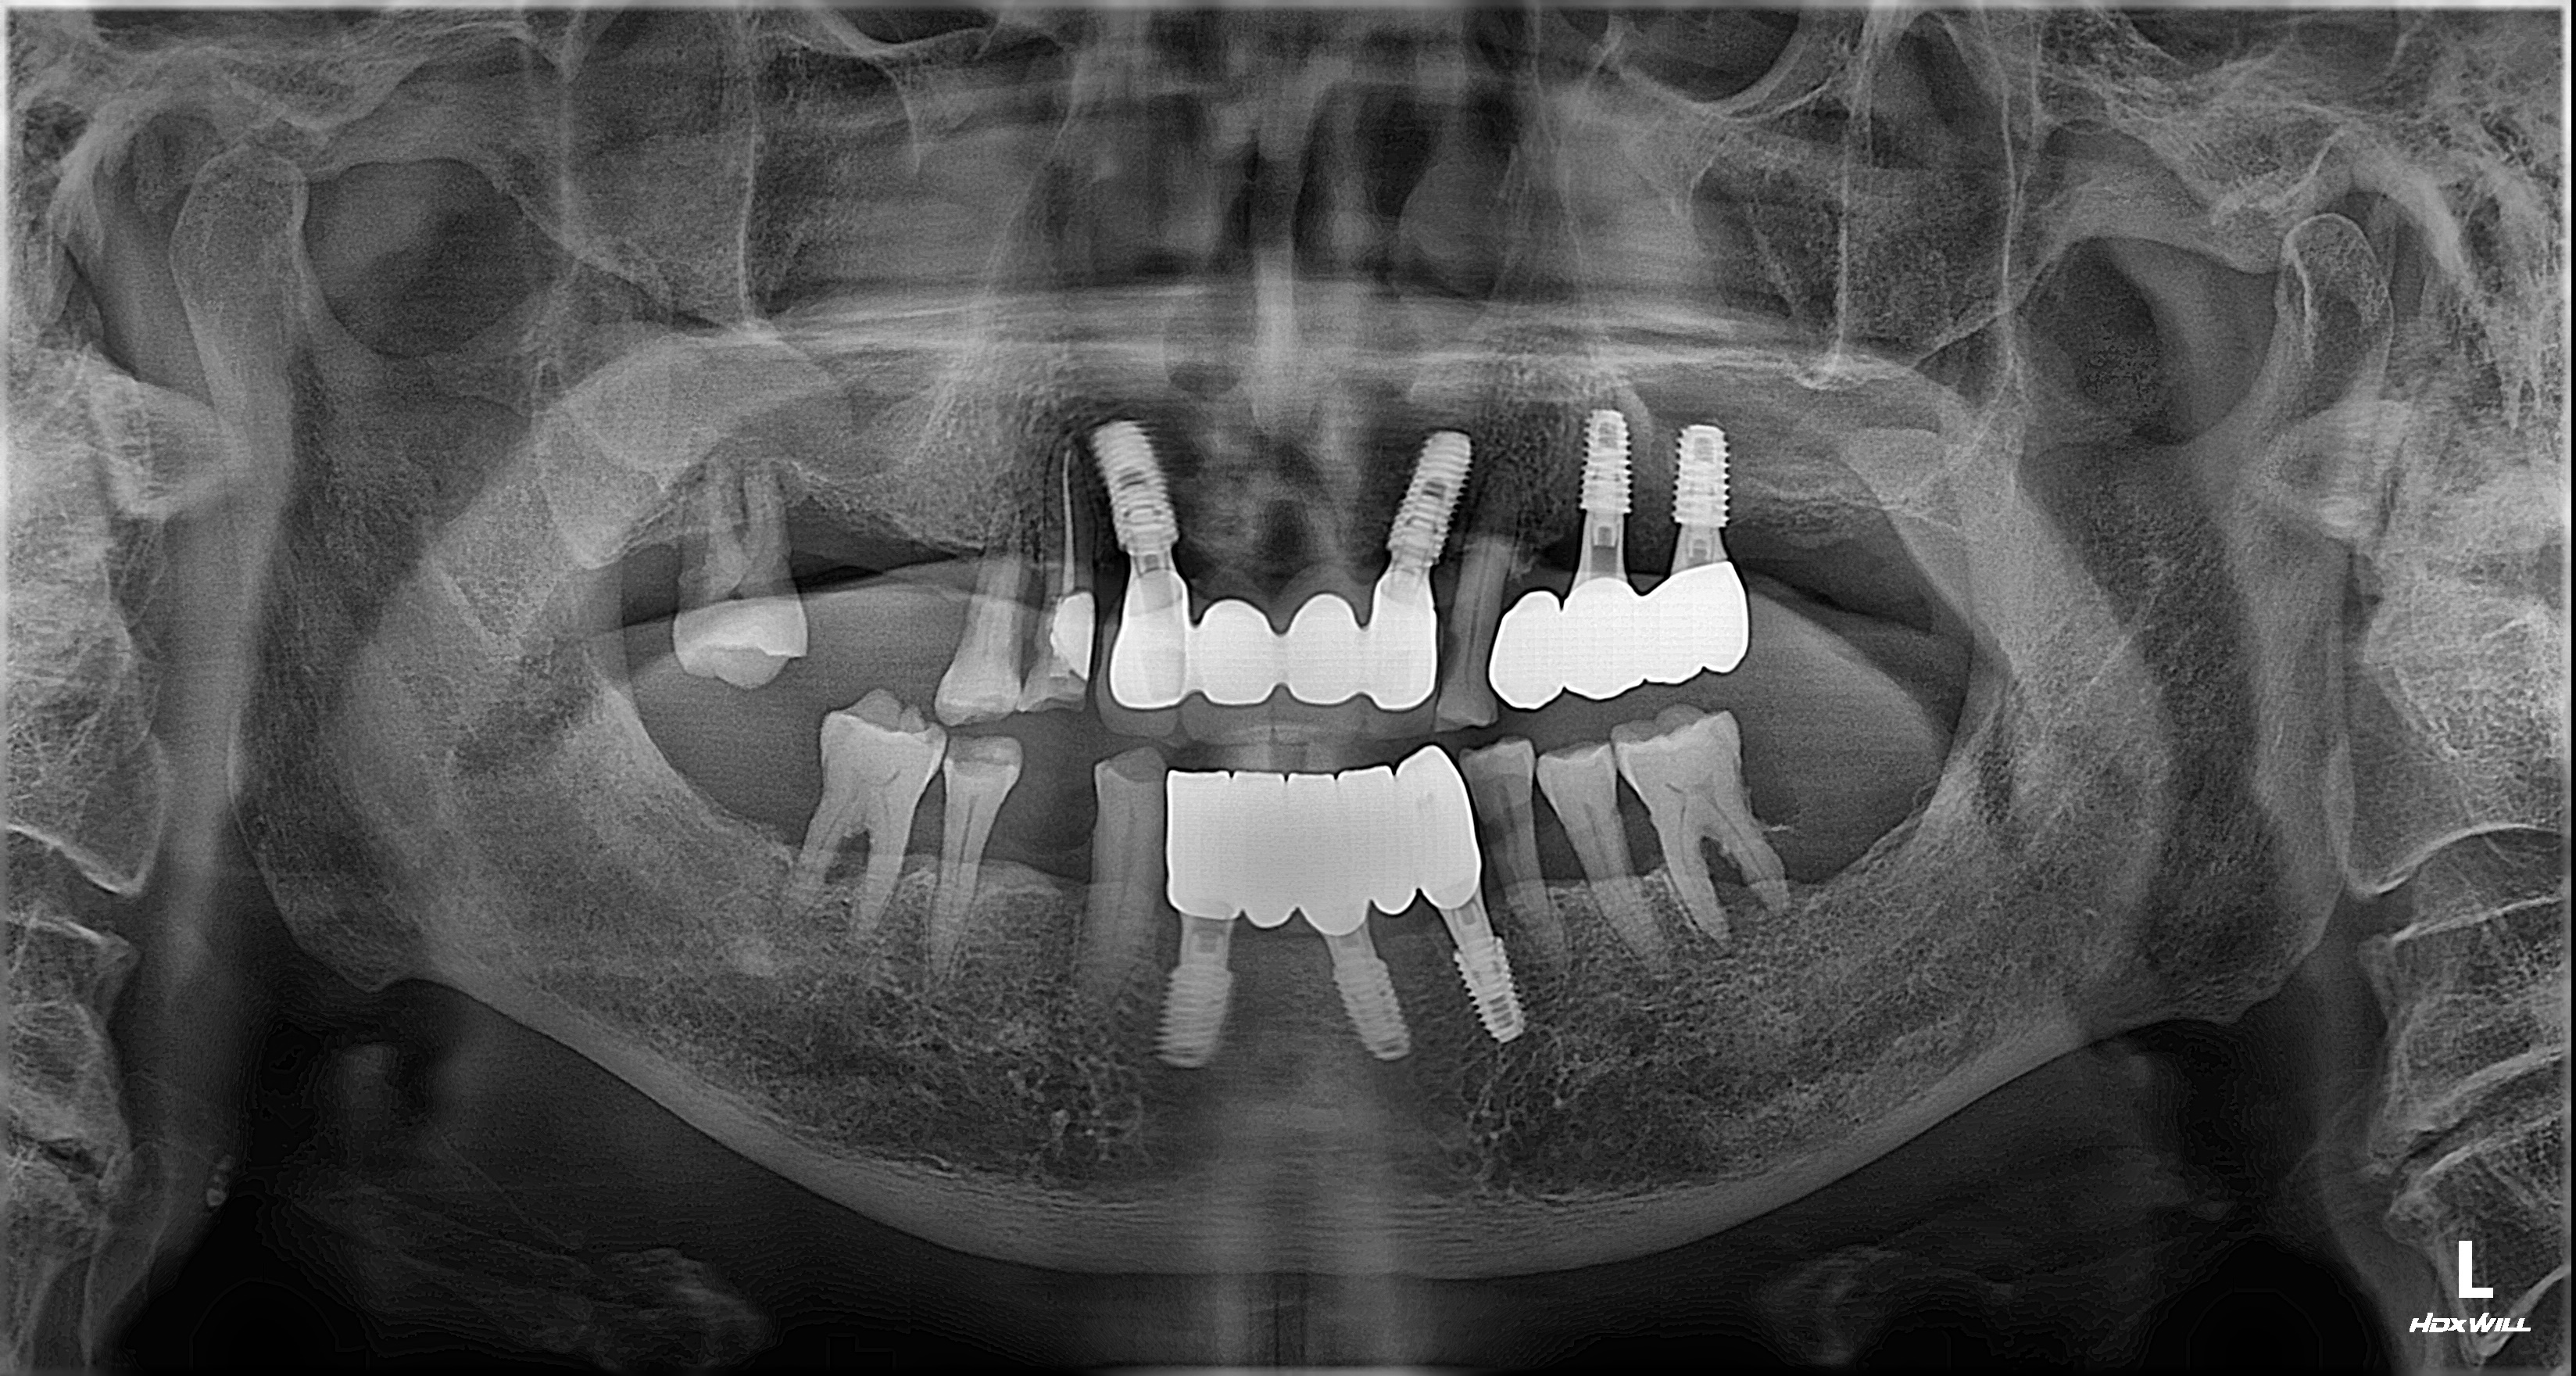

2026년 3월 5일에 촬영된 최종 방사선 사진입니다.

첫 내원일로부터 약 6개월간의 치료 과정이 안정적으로 마무리되었습니다.

하악 전치부에는 임플란트를 지지대로 삼아 브릿지 형태의 보철물이 체결되었고, 뼈가 부족했던 좌측 상악 어금니 부위 역시 상악동 거상술을 통해 튼튼하게 보철물이 완성되었습니다.